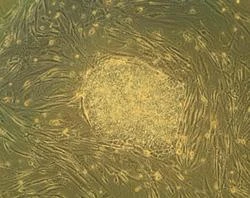

Vatican daily: Embryonic stem cells only create false hope

Research demonstrates that embryonic stem cells are not an effective resource for treatment and create false hope for a cure,... Read more